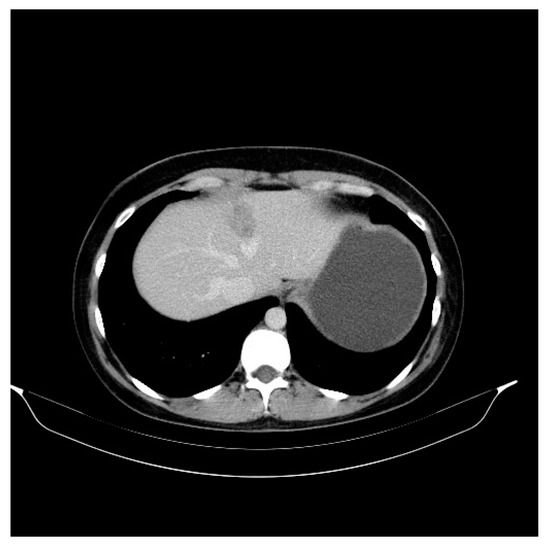

2. Case Presentation